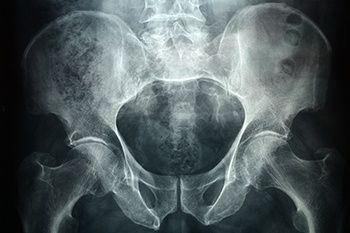

Рентген копчика

Копчиковая кость представляет собой нижний отдел позвоночного столба человека, который состоит из 4-х — 5-ти сросшихся между собой рудиментарных позвонков. Он выполняет целый ряд важных функций, включая распределение нагрузки на анатомические структуры таза. Рентген копчика является важной составляющей диагностики заболеваний этой кости.

Рентгенографию копчиковой кости проводят в двух проекциях, но для того, чтобы снимки были максимально чёткими, пациенту необходимо предпринять ряд мер. Подготовка к рентгену копчика заключается в исключении из рациона пищи, способствующей газообразованию: бобовые, молочные продукты, капуста, прочее. Их не стоит потреблять в течение 2‒4 дней до процедуры. Нередко рекомендуют провести очистительную клизму или назначают приём активированного угля и других фармакологических препаратов-энтеросорбентов.

Перед проведением процедуры пациента попросят снять с себя любые металлические предметы. Процедура проводится в положении лёжа; при этом, в зависимости от ситуации, рентгенолог выбирает определённую проекцию, в соответствии с которой просит пациента занять определённое положение:

Что показывает рентген копчика?